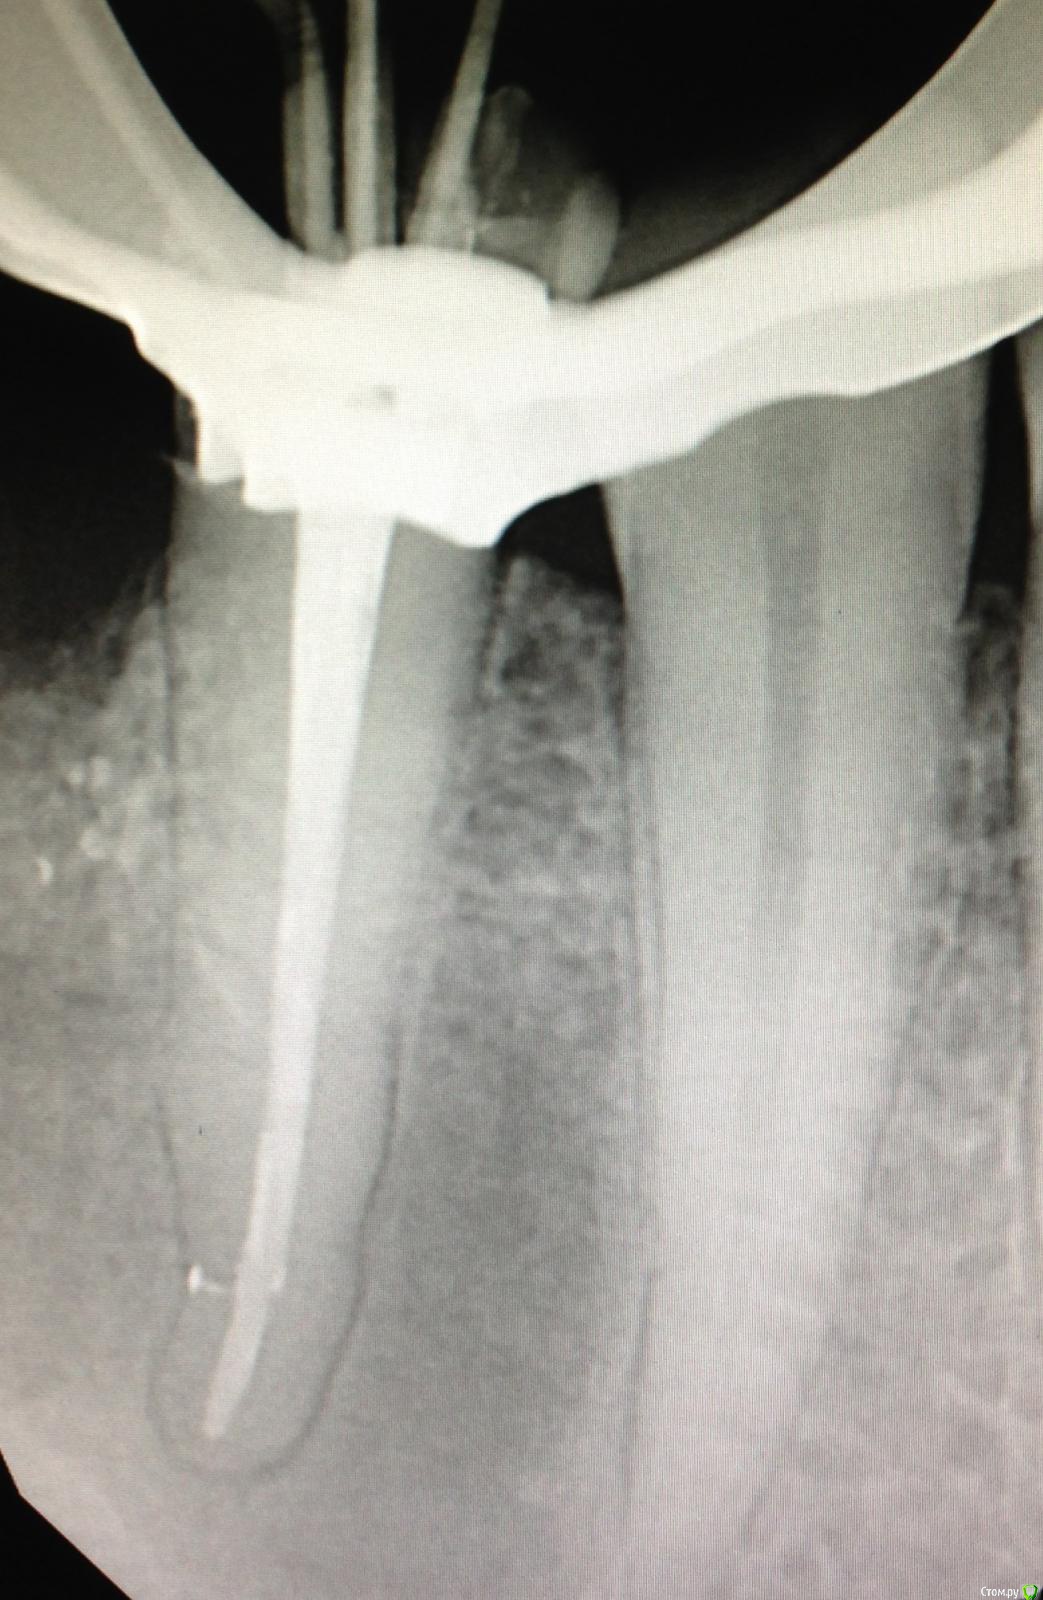

SSTi Опубликовано 27 декабря, 2014 Автор Поделиться Опубликовано 27 декабря, 2014 Вот так бывает. Красота. 21 оставил пока кальций. 11 запаковал. 2 Ссылка на комментарий